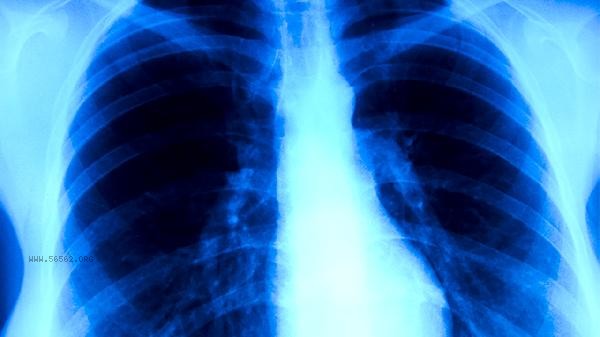

It is recommended that patients with old pulmonary tuberculosis undergo chest CT and sputum culture re examination before physical examination to confirm the absence of active lesions. It is necessary to maintain sufficient sleep and a balanced diet in daily life, and engage in appropriate aerobic exercise to enhance lung function. Actively explain the history of tuberculosis to doctors and provide complete medical records during physical examination, which is helpful to accurately evaluate the physical examination results.